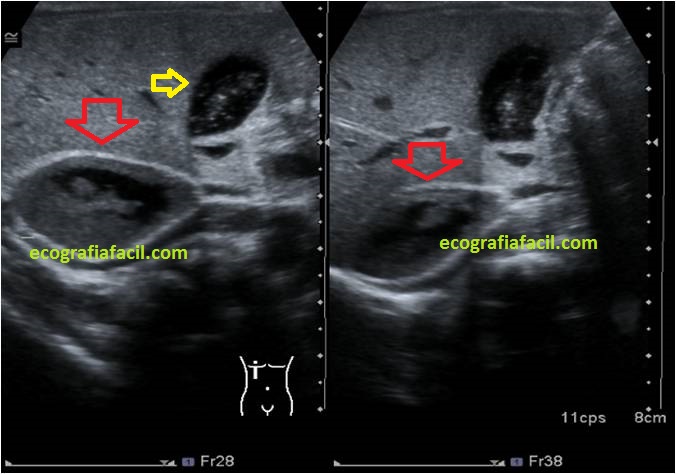

En este breve post de este domingo te explico sobre una imagen habitual del protocolo de Abdomen, la anatomía habitual que podemos encontrar y además semiología habitual y muy variada que podemos encontrar. Te valdrá de repaso de conceptos básicos de la técnica ecográfica.

Quiero que compares ambas, una sin y otra con indicaciones y así primero podrás hacer un test de lo que ves y luego consultar los resultados en el comentario de imagen que hago a continuación.